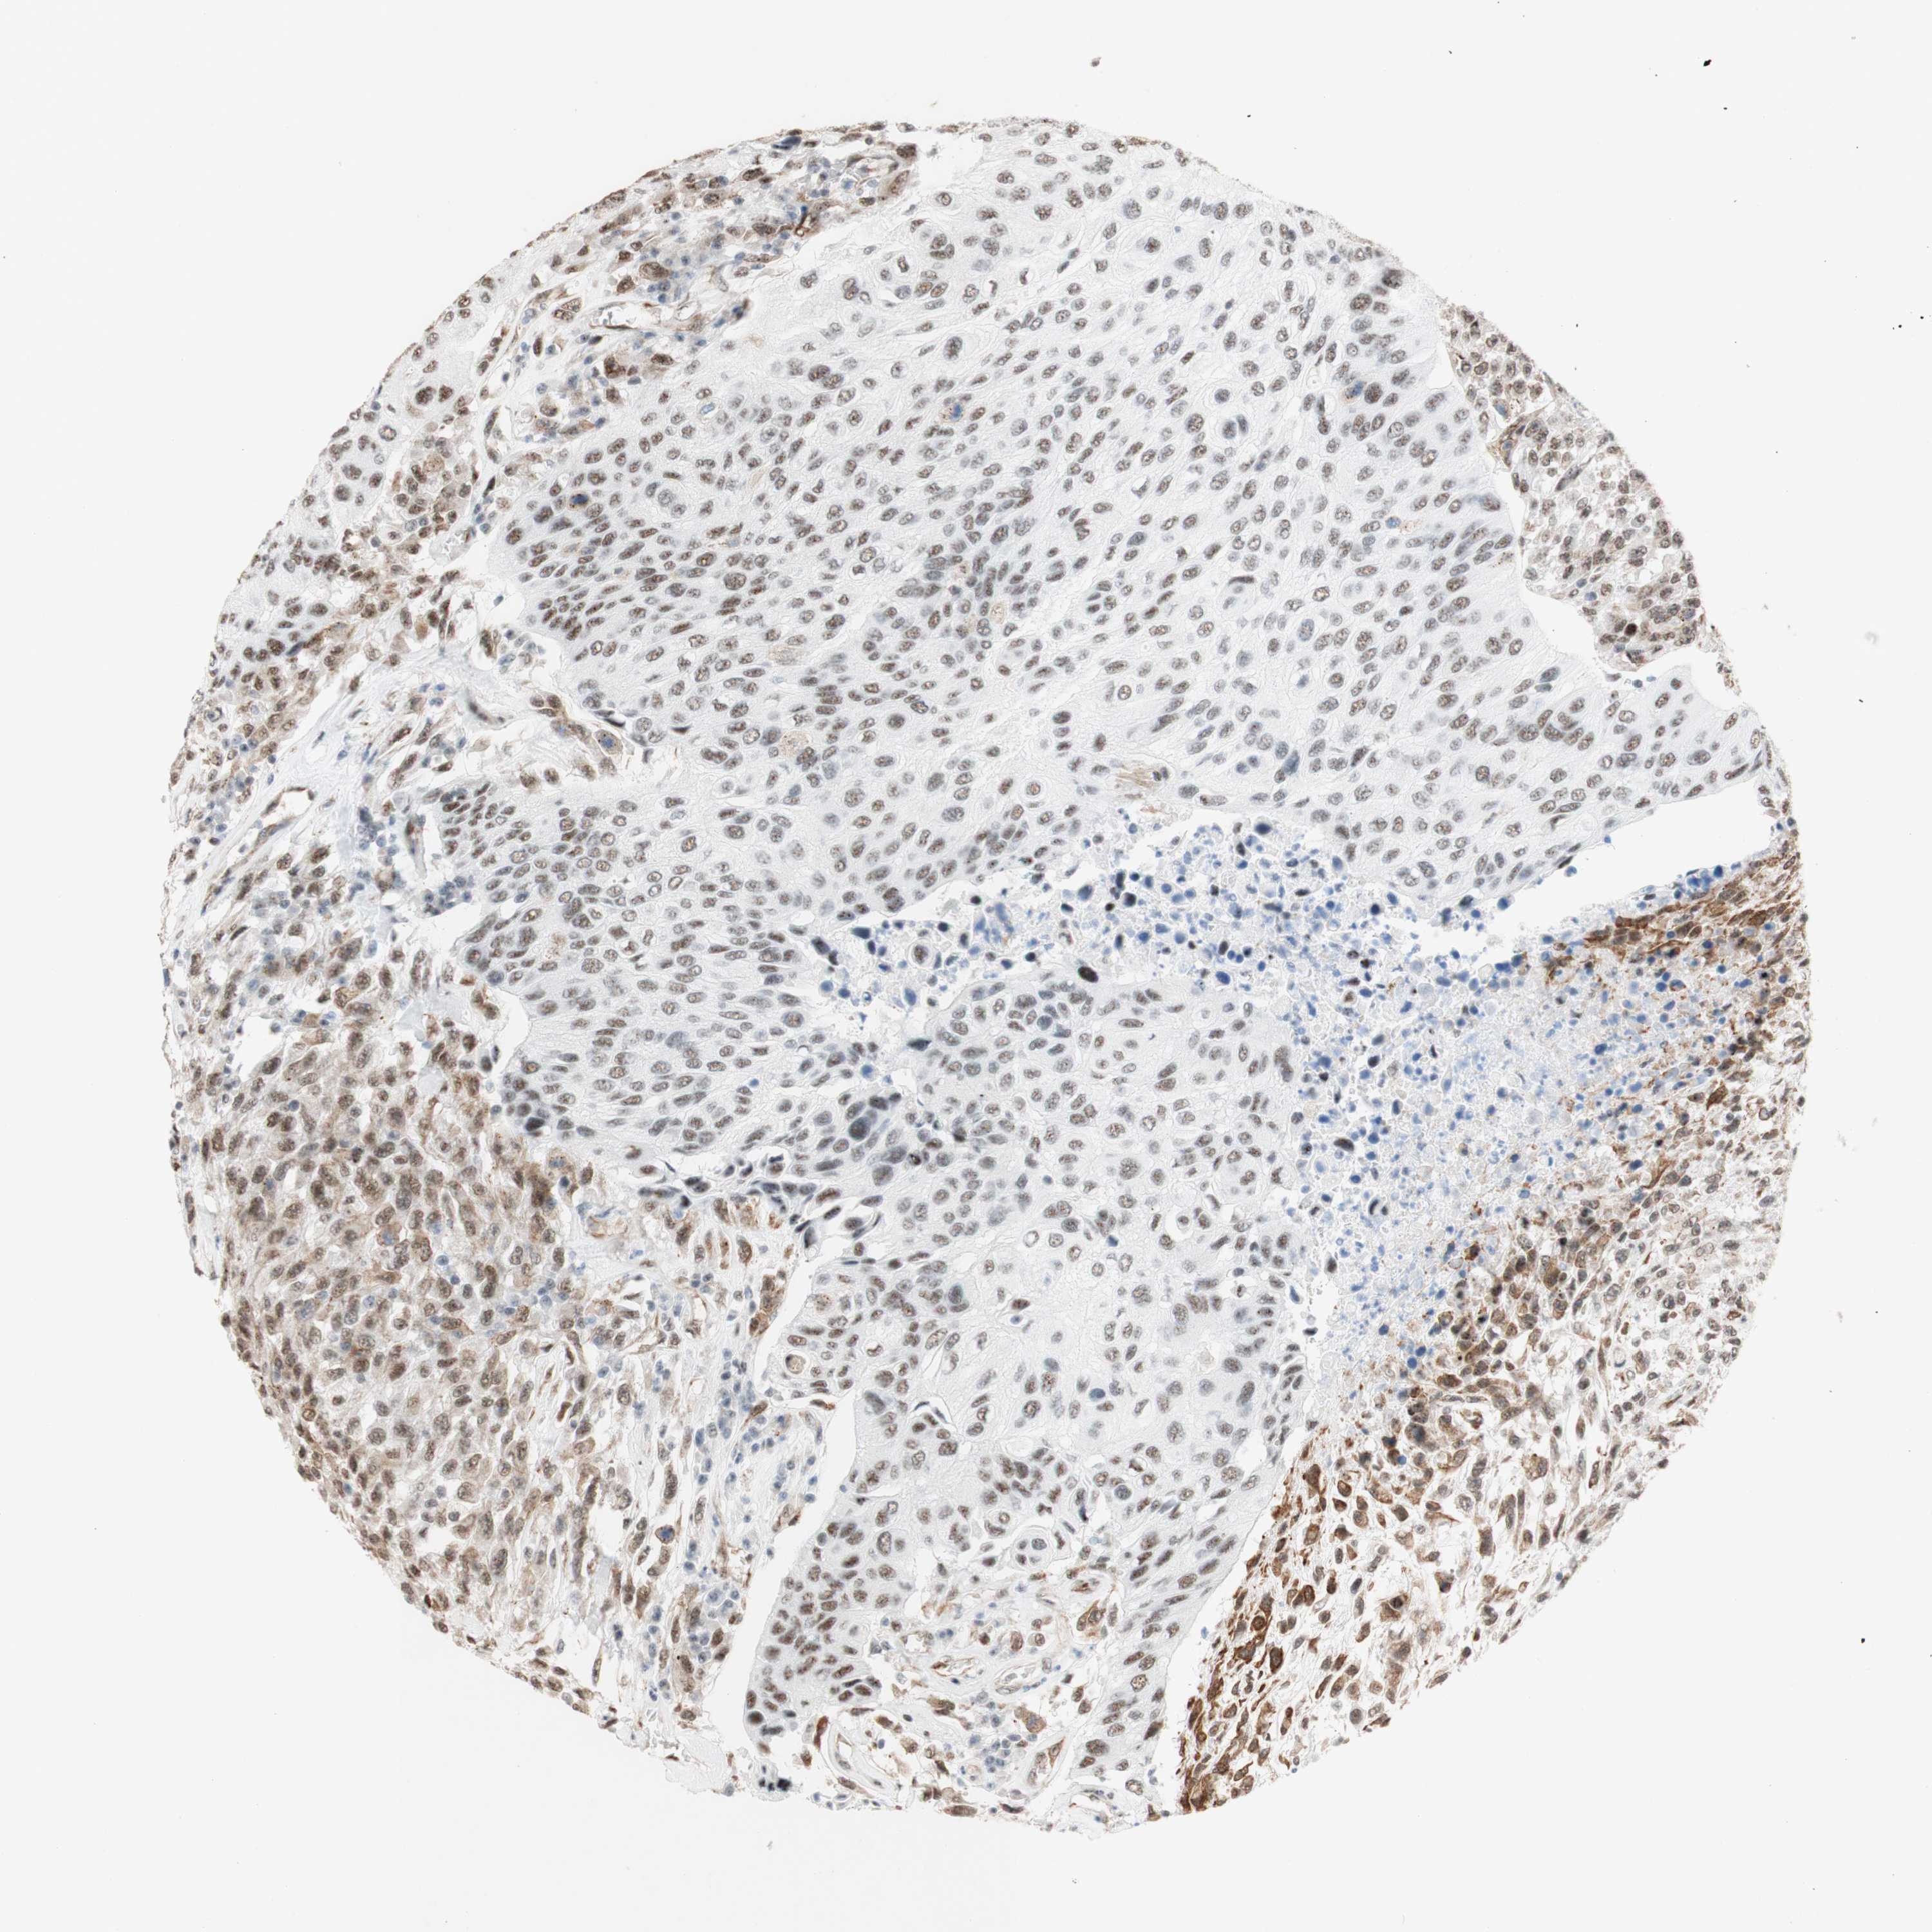

UROTHELIAL CANCER - Protein expressioni

A mouse-over function shows sample information and annotation data. Click on an image to view it in a full screen mode. Samples can be filtered based on level of antibody staining by selecting one or several of the following categories: high, medium, low and not detected. The assay and annotation is described here.

Note that samples used for immunohistochemistry by the Human Protein Atlas do not correspond to samples in the TCGA dataset.

Antibody stainingi

Antibody staining in the annotated cell types in the current human tissue is reported as not detected, low, medium, or high, based on conventional immunohistochemistry profiling in selected tissues. This score is based on the combination of the staining intensity and fraction of stained cells.

Each image is clickable and will lead to virtual microscopy that enables deeper exploration of all samples and also displays staining intensity scores, fraction scores and subcellular localization as well as patient and tissue information for each sample.

Antibody HPA011352

Antibody CAB012273

Staining

High

Medium

Low

Not detected

Intensity

Strong

Moderate

Weak

Negative

Quantity

>75%

75%-25%

<25%

None

Location

Nuclear

Cytoplasmic/membranous

Cytoplasmic/membranous,nuclear

Urothelial carcinoma, Low grade

Urothelial carcinoma, High grade